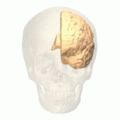

![]() Medial surface of left cerebral hemisphere. (Cuneus visible at left in red.) | |

Position of cuneus(red) of left cerebral hemisphere.

Medial surface of left cerebral hemisphere. Cuneis is visible at left in green.